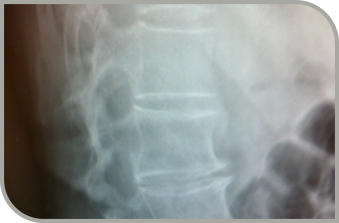

1988 Reflexzonen am Fuss Marquardt 1990 Feingefühl & Medialiät Bonanomi 1992 Reiki Grad I und II Bern 2005 - 2014 Kantonsspital Liestal Chrirurgie BH II 2007 rhytmische Einreibungen Ita Wegmann Klinik 2008 Röntgenbilder lesen Bodyfeet Aarau 2008 BeBo Beckenboden Training von Rütte Bennwil 2004/06/07/09 Fastenwoche Kloster Müstair W. Maschke U.Nolfi 2009 Uni Basel Sektion in Patologie ZVMN Hölstein 2011 VDMS wichtigkeit der Rumpfstabilität 2012 KSLi Sterben im Spital 2014 2015 Myofasziales Taping: Physio Training Academy